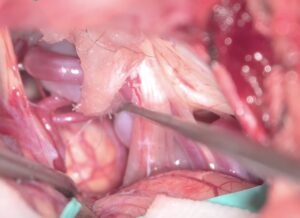

53歳女性の左顔面痙攣を手術しました。仰臥位-外視鏡手術を行いました。セッティングに慣れて来たため、とてもスムーズに終わりました。術後軽度の左顔面神経麻痺が出ましたが、耳鼻科の電気生理検査では回復が予想される結果でした。外来で軽快傾向にあります。